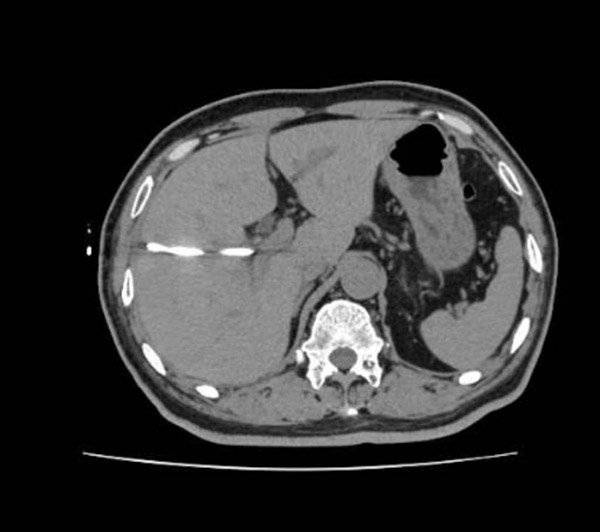

图为患者十二指肠部位的穿孔 十二指肠穿孔属于外科急症,别说伴有如此高的黄疸,单单就是腹腔内的消化液继发感染,就随时可能要了老周的性命,必须马上处理!但是手术方式 怎么选择呢?患者胆管肿瘤需要做“胰头十二指肠切除术”,这可是普外科里“创伤最大、并发症最多”的手术! 手术不仅需要切掉胆囊、部分胆管、十二指肠、部分胃以及胰腺头部组织,还需要重建消化道的连续性,将胆管、胰腺、胃和小肠重新吻合在一起,而此时,已经发 生消化道穿孔的腹腔内,很可能已经产生了严重的感染,加上目前380的高黄疸,如此复杂重大的手术将使病人面临更加复杂、危险的境况。术后全身感染、吻合 口漏、肝衰竭等并发症将成为医患双方的梦魇,手术难谈成功。 当务之急,一是引流胆汁,二是解决解患者的急性穿孔,三是尽量减少对进一步肿瘤根治手术的影响。这个三合一的难题,是否有解呢?王玉文心里已经有谱了。 图为王玉文为患者行腹腔镜微创术 凌晨一点,患者被紧急推进手术室,进行了腹腔镜下十二指肠穿孔修补+经皮经肝胆汁引流术。 先下胆道引流管,把积在胆道里的胆汁引流出来。由于堆积在胆道里时间过长,引流出来的胆汁已经呈现墨绿色,如同尚未浇灌的沥青。胆汁成功引流之后,腹腔镜下修补穿孔的“重头戏”就来了。 腔镜镜头从肚脐进入,手术缝针从肚皮上另外2个小孔进入腹腔,找到并缝闭十二指肠穿孔,大量盐水冲洗腹腔清除脓液……手术持续了80分钟,干脆利落,非常成功! 图为患者接受胆道引流术后CT 就这样,王玉文团队以最小的创伤(腹腔镜微创技术),同时解决了老周的两大急症。术后一周,白细胞、降钙素原、胆红素等都在下降,老周身体恢复得很快。经过初步的评估,老周很快能可以接受胆管肿瘤切除手术了。 王玉文几次查房,老周都激动地握着王玉文的手,“小创伤,治大病,王主任真厉害,六院真厉害!”。老周的家属也当即拍板——“六院有这么好的大夫,咱们家属还有啥不放心的,胆管肿瘤切除的大手术,咱也得在六院做!” 谈到这次手术,王玉文主任说,“医生不止是要治好眼前的急症,更要针对患者的病程做通盘考虑,选择最适合个体的治疗方式,因为手术刀下的患者,首先是一个活生生的人”。 多年来,沈阳六院立足肝胆胃肠传统优势,坚持“大综合、强专科”的发展道路,实现了多学科协同并进,努力将“大医精诚”的仁心仁术,体现在每一次患者救治中,满足广大市民的就医需求,让沈阳人拥有健康生活! 供稿:外二科 编辑:宣传科 审核:王磊石